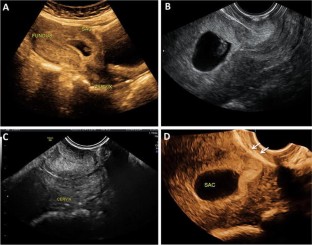

Cesarean scar pregnancy (CSP) is a rare kind of ectopic pregnancy implanted in the previous cesarean scar and has an increasing incidence over the past 30 years. As the suspicion is low, the diagnosis may be delayed or misinterpreted in ultrasound, leading to treatment strategies that might end up in uterine rupture or hysterectomy. The objective here is to review the ultrasound findings in CSP with varied presentations. Transabdominal and transvaginal sonography combined with color Doppler is a reliable tool for the diagnosis of CSP. When the gestational sac is seen in lower part of the uterine cavity, differentiation between threatened miscarriage, cervical pregnancy and CSP could be difficult. Not all cases of CSP present with typical ultrasound findings and a high index of suspicion is needed for diagnosis in these cases. An attempted curettage or MTP pill taken in an undiagnosed CSP often alters the typical findings. The possibility of CSP should also be considered in cases presenting with abnormal uterine bleeding and have a prior history of cesarean section. With lack of awareness about this condition, the diagnosis can often be missed either with MRI or in ultrasound. Correct interpretation and timely diagnosis save the mother from life-threatening complications and also preserves future fertility.

Fig. 4